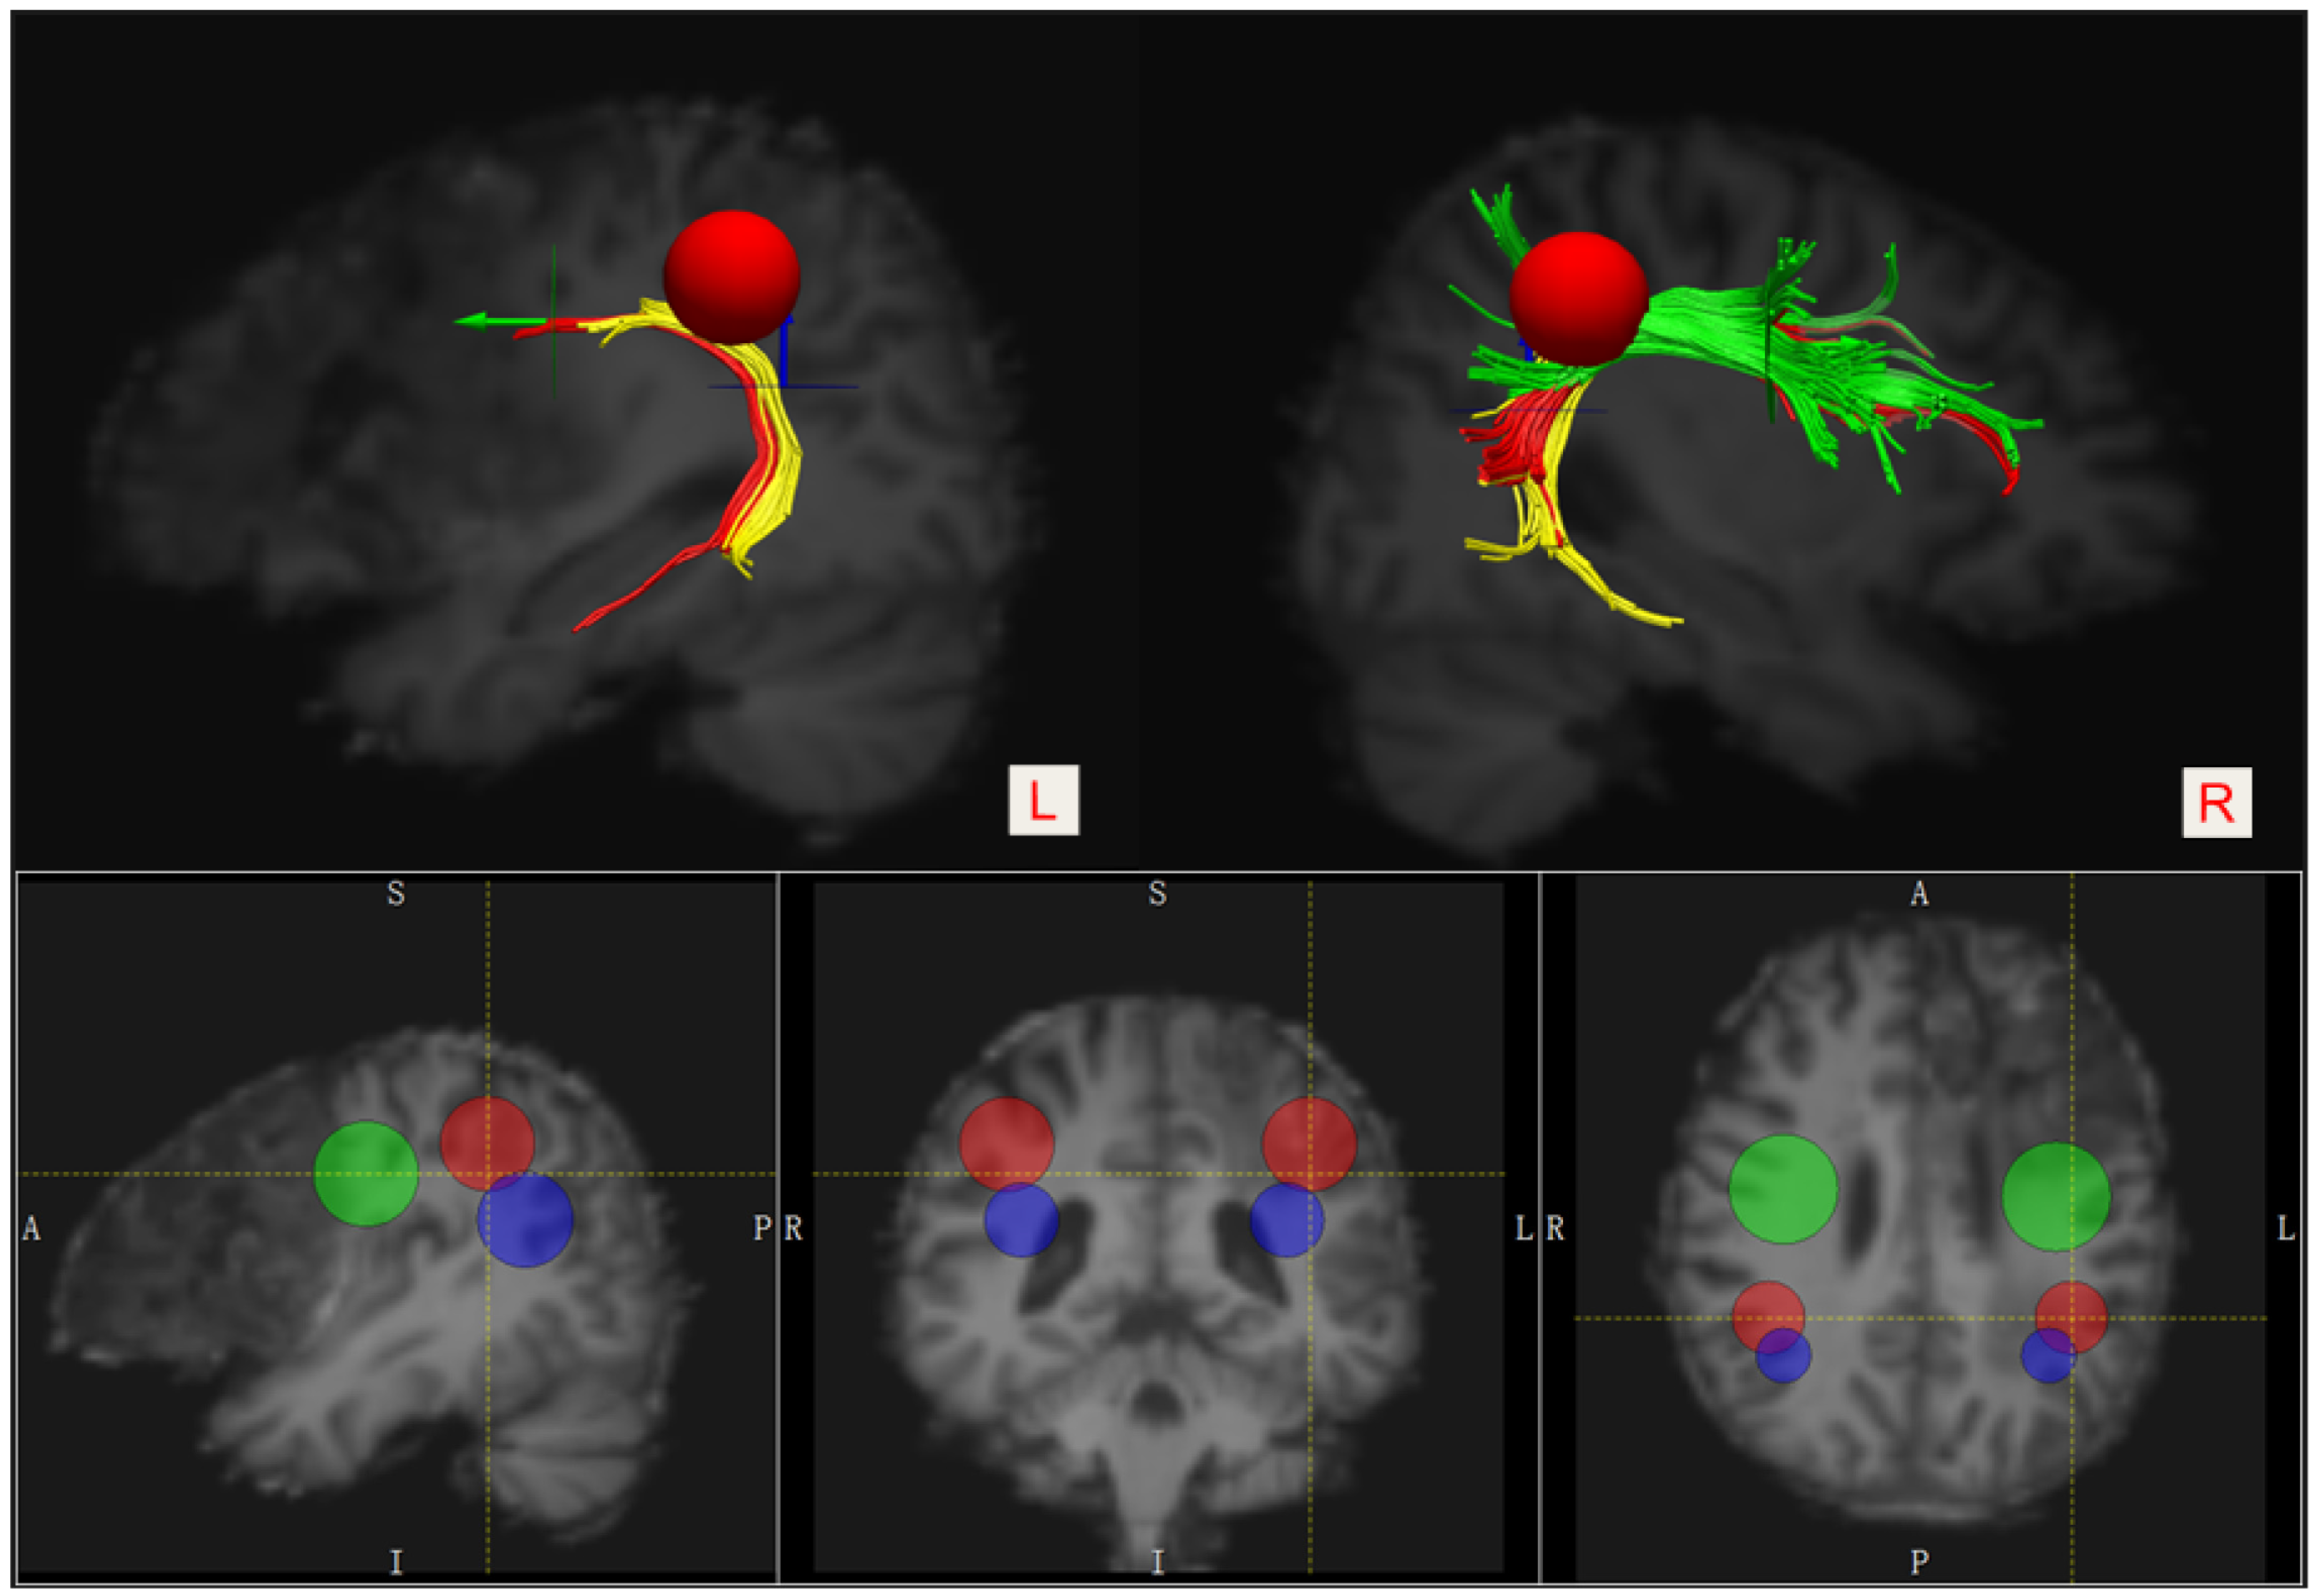

3. Diffusion Tensor Imaging and Tractography Evaluation